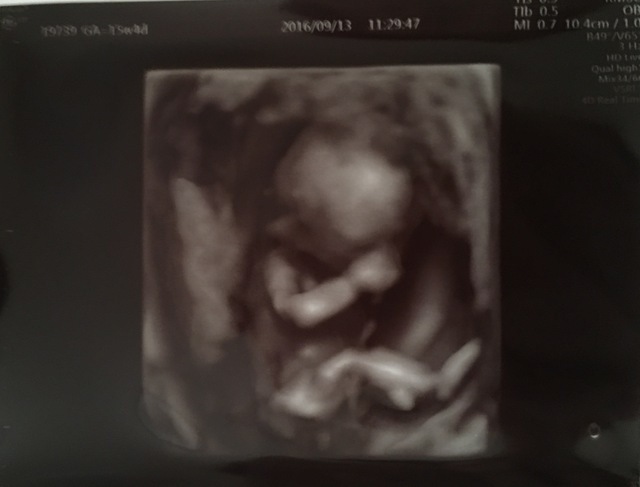

15週1日(15w1d・女の子)|yellowp さん(23歳)

エコー写真撮影時のエピソード:

全体がきれいにうつってるのはこの1枚です。1ヶ月後には写真ではおさまらない大きさに。恥ずかしがり屋でなかなか顔を見せてくれませんでした。

通っていた産科が3D?4D?だったので毎回見るのが楽しみでした。顔がはっきり見えるエコーがありますが、なんとなく面影があるかなという感じです。